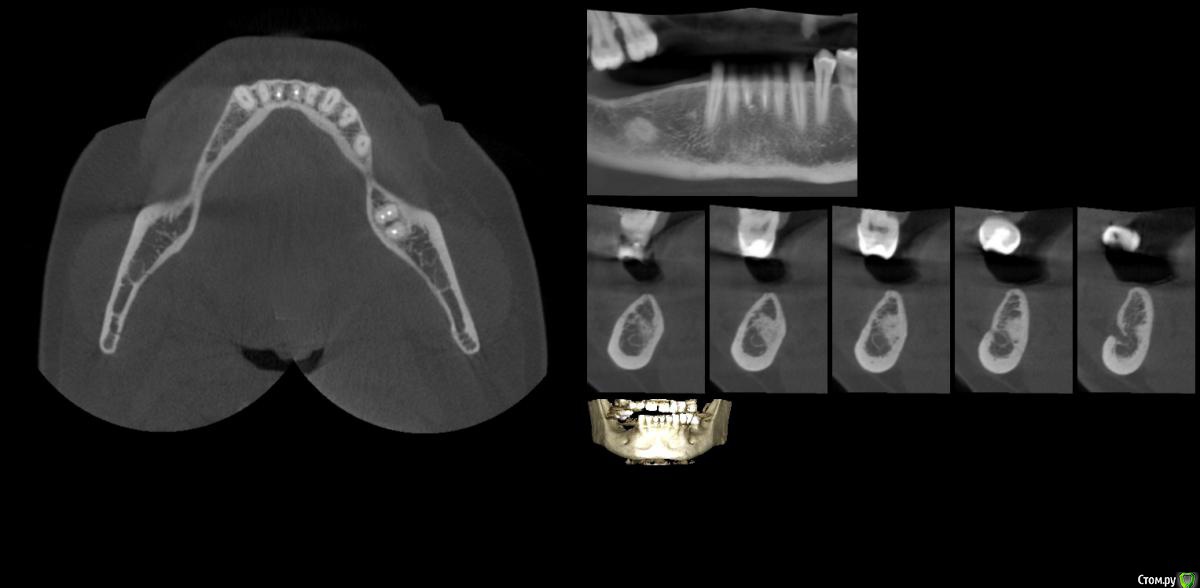

gum Опубликовано 28 февраля, 2016 Поделиться Опубликовано 28 февраля, 2016 . Здравствуйте коллеги. Планируется имплантация данной области. Скажите пожалуйста: 1. Остеома ли это и можно ли имплантировать в данном случае? 2. Если можно, то какой протокол (сразу ставить имплантат или формировать ложе и ставить отсрочено)? А также до нч канала около 1 мм при установке имплантата, на каких оборотах лучше работать, чтобы снизить компрессию. Спасибо. Ссылка на комментарий

Maxfac Опубликовано 28 февраля, 2016 Поделиться Опубликовано 28 февраля, 2016 Очаг склероза, он же dense bone island. Я бы вкрутился. 3 Ссылка на комментарий

Alexey Doc Опубликовано 28 февраля, 2016 Поделиться Опубликовано 28 февраля, 2016 Тем более что только часть поверхности имплантата( не более половины) будет с этим участком в контакте Ссылка на комментарий